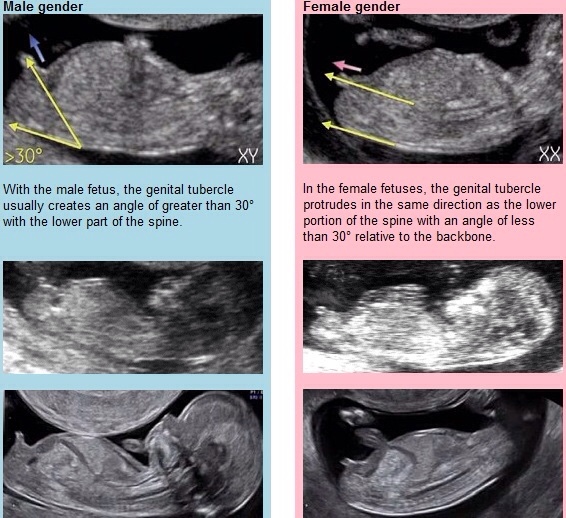

Jedyna uznana metoda na wczesnym etapie ciazy na USG jest kat odchylenia wyrostka plciowego. Bylo sie o to zapytac :)